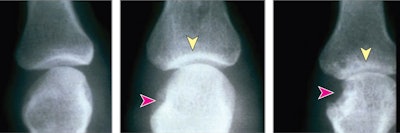

Rheumatoid arthritis (RA) is a chronic disease characterized by inflammation in the synovial lining of joints. This inflammation causes joint space narrowing and bone erosion, which can lead to joint deformity and disability. The disease is typically diagnosed on x-rays, but identifying it can be challenging without an expert's interpretation, the authors wrote.

Participants were tasked with developing automated methods to quickly and accurately quantify overall RA damage (subchallenge 1), joint space narrowing (subchallenge 2), and erosion (subchallenge 3) from x-ray images of hands and feet.

To develop the algorithms, teams were provided with 674 sets of patients x-rays from two RA clinical trials. The images had been annotated by experts to indicate normal and damaged joints. Sharp-van der Heijde scores (SvH), or "sharp scores," were used as measures of erosion and joint space narrowing on the images on a scale from 0 to 10.